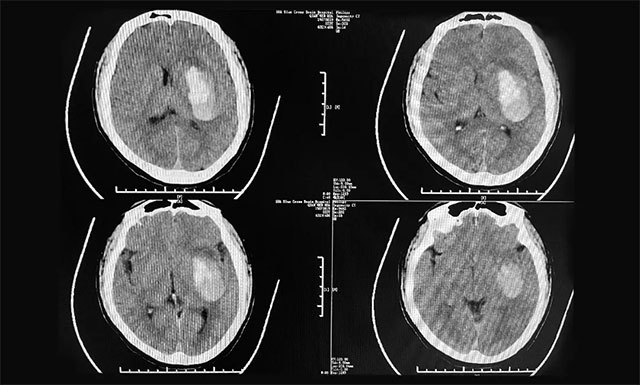

▲ 患者突發(fā)腦出血,致使其右側(cè)偏癱并昏迷不醒

在醫(yī)院,小文緊急進(jìn)行了頭部CT檢查,影像提示:左側(cè)基底節(jié)區(qū)腦出血,當(dāng)時(shí)小文人已經(jīng)陷入昏迷,右側(cè)肢體偏癱,手術(shù)風(fēng)險(xiǎn)大,醫(yī)院建議保守治療并及時(shí)予以對癥藥物治療。但鑒于丈夫小文病情危重,家人心急如焚,妻子林女士與家人商量后,決定轉(zhuǎn)院進(jìn)一步手術(shù)治療,隨后于當(dāng)天下午,慕名轉(zhuǎn)診于上海藍(lán)十字腦科醫(yī)院,收治于神經(jīng)外科6B病區(qū)。

對于小文當(dāng)日入院情形,潘仁龍主任仍記憶猶新:“小文屬于急性腦出血,當(dāng)天下午4:30就轉(zhuǎn)入了藍(lán)十字腦科醫(yī)院,為了方便治療和及時(shí)手術(shù),直接走醫(yī)院腦卒中綠色通道。他來院時(shí)神志模糊,自動(dòng)睜眼,無言語,其右側(cè)偏癱嚴(yán)重,上下肢肢體肌力僅有1級,情況危急,結(jié)合其頭部影像檢查,其出血約為40ml左右,需及早手術(shù)。”